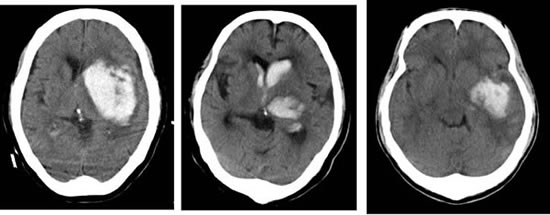

뇌출혈은 뇌혈관이 터지면서 혈액이 뇌 조직이나 뇌를 둘러싼 공간에 쏟아져 나오는 상태를 말합니다. 혈액이 뇌세포를 압박하거나 손상시켜 뇌 기능에 장애를 일으키며, 급성 응급질환에 해당합니다.

- 증상 인지 후 1시간 이내 병원 도착이 가장 바람직하며, CT, MRI 검사로 즉시 진단 후 치료 결정이 이루어져야 합니다.